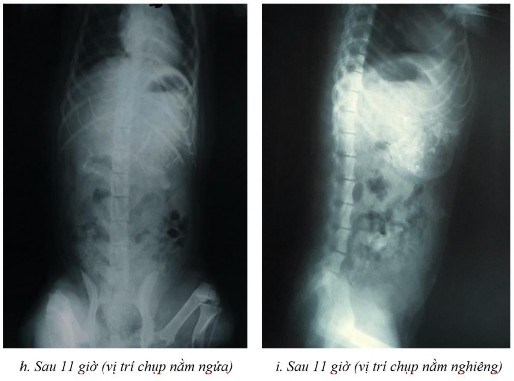

Phụ lục 5.1. Hình ảnh X-quang chó 2 ở thời điểm (a) sau 2 giờ ở vị trí nằm nghiêng, (b) sau 4 giờ ở vị trí nằm ngửa, (c) sau 4 giờ ở vị trí nằm nghiêng, (d) sau 7 giờ ở vị trí nằm ngửa, (e) sau 7 giờ ở vị trí nằm nghiêng, (f) sau 9 giờ ở vị trí nằm ngửa, (g) sau 9 giờ ở vị trí nằm nghiêng, (h) sau 11 giờ ở vị trí nằm ngửa và (i) sau 11 giờ ở vị trí nằm nghiêng